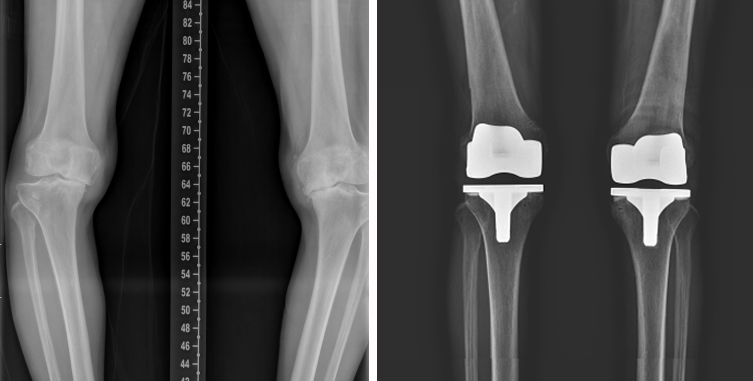

반면 무릎 안쪽 관절만 국한해 심하게 닳은 경우에는 인공관절 부분치환술이 적합하다. 손상된 부위만 5~7cm 정도의 최소 절개를 통해 교체하기 때문에 출혈이 적고 회복이 빠른 장점이 있다. 무릎 전체가 광범위하게 손상된 4기 환자라면 인공관절 치환술, 즉 전치환술이 필요하다.

이는 10cm 내외 절개 후 손상된 대퇴골과 경골 관절면을 정교하게 다듬고 특수 금속과 고강도 플라스틱으로 제작된 인공관절을 삽입하는 방식이다. 수술 시간은 약 1시간 30분 내외이며, 관절 정렬을 바로잡아 O다리 교정 효과도 기대할 수 있다.